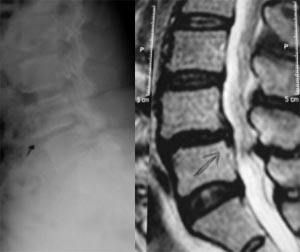

A.後伸位;B.中立位;C.前屈位對於滑脫程度較重者應加拍左右斜位片,與峽部裂性脊椎滑脫相鑑別。(見圖) 腰椎側位像顯示腰4退行性滑脫伴腰4~5節段性不穩定(水平移位4mm、角度變化24°)

2.CT、MRI 主要觀察椎管水平、矢狀斷面上的變化,包括椎管狹窄、神經根通道狹窄的程度、硬膜囊受壓的情況、椎間盤退變的程度、以及黃韌帶、關節突增生、肥厚的變化等。MRI被認為是目前檢查脊髓和神經無創手段的金標準;除此之外,應該注意在MRI檢查中觀察鄰近節段,尤其是上位間盤的退變情況,對於評估腰椎的整體狀態、融合節段的選擇,具有重要意義。